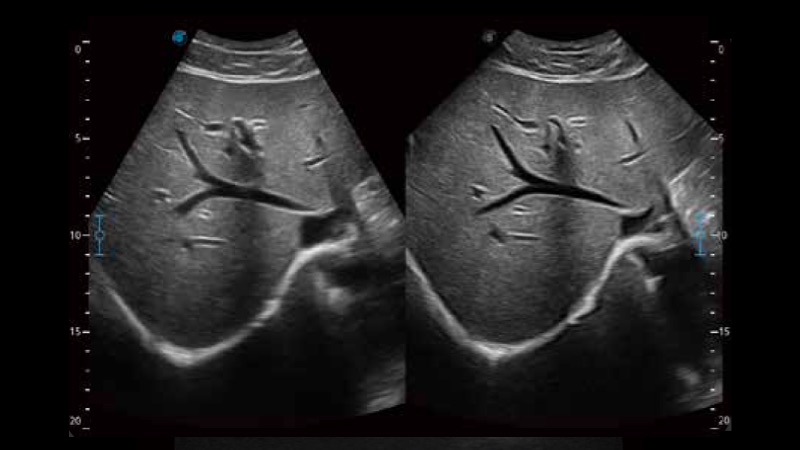

扩展成像技术

凸阵、线阵和相控阵探头进行实时扫描时,开启扩展成像模式,可以扩展超声图像视野,以便更完整地查看大的病灶或组织器官的解剖结构。

临床图像